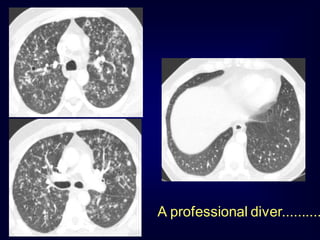

A professional diver..........

.......after cessation of smoki